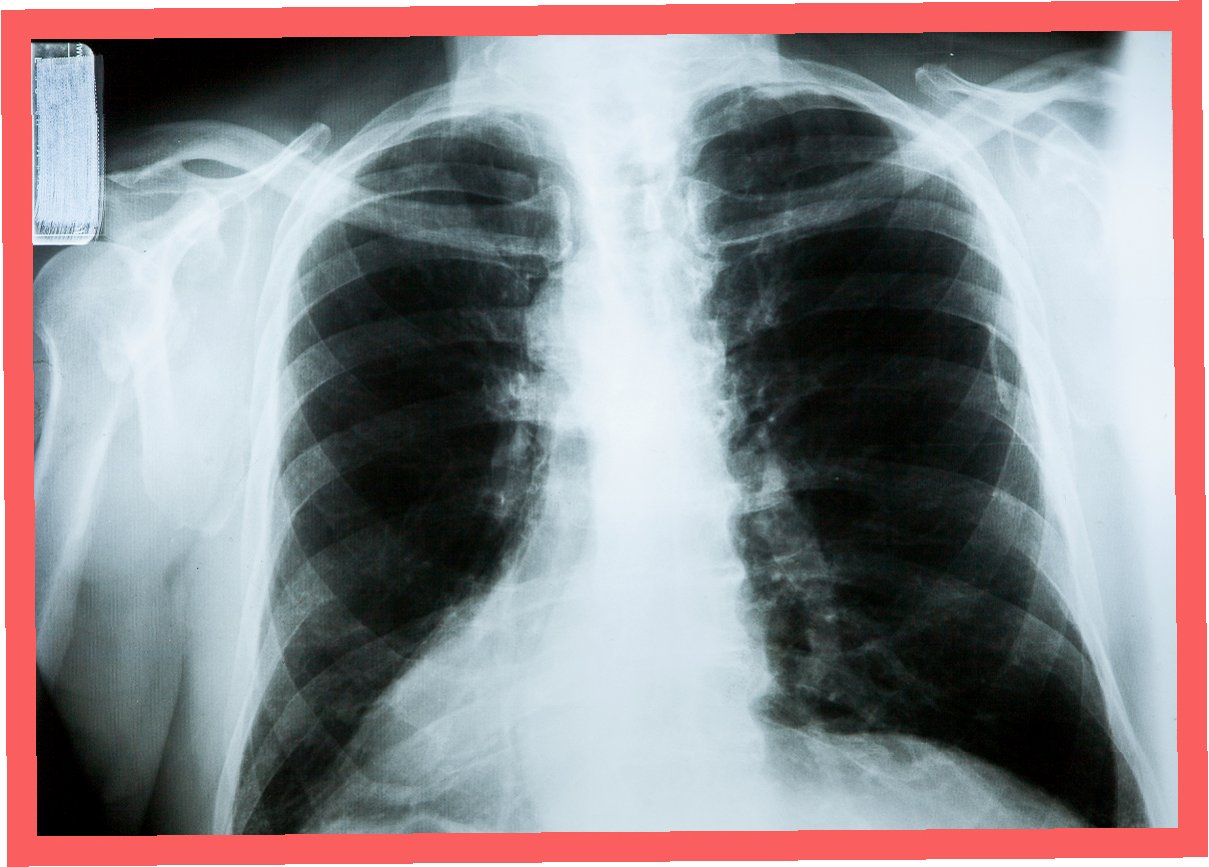

2019년부터 시작된 원인 불명의 밤마다 반복되는 고열로 병원을 찾은 사이먼스 씨는 CT 검사 결과 충격적인 사실을 마주했습니다. 사고 당시 폐 깊숙이 들어간 먼지 파편이 체외로 배출되지 못한 채 딱딱하게 굳어 왼쪽 폐 기관지를 완전히 막고 있었던 것입니다. 그는 “기계에 깔려 움직일 수 없을 때 먼지를 들이마셨는데, 그게 깊이 들어가 굳어버렸다”고 당시 상황을 설명했습니다. 의료진은 외상으로 인해 체내에 남은 이물질이 장기간에 걸쳐 칼슘으로 둘러싸여 석회화가 진행된 것으로 판단했습니다. 정밀 검사 결과, 좌측 폐는 5년간의 감염으로 기능을 완전히 상실한 상태였습니다.

의료진은 처음에는 석회화된 부분만 제거하려 했으나, 손상 범위가 너무 넓어 폐 전체를 적출해야 한다는 결론에 이르렀습니다. 사이먼스 씨는 결국 왼쪽 폐를 떼어내는 수술을 받았습니다. 그는 “작은 먼지 한 톨이 내 인생을 이렇게 바꿀 줄 몰랐다”며 “수술 동의서에 서명하던 순간이 인생에서 가장 무거웠다”고 심경을 토로했습니다. 이처럼 외상으로 체내에 남은 이물질은 장기간에 걸쳐 석회화되며 염증이나 조직 괴사를 일으킬 수 있습니다. 특히 폐 조직은 통증 수용체가 적어 초기 증상 인지가 어렵고, 뒤늦게 발견되는 경우가 많아 주의가 필요합니다.